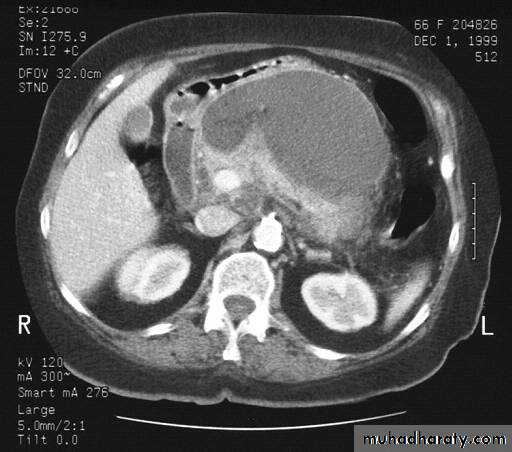

CT abdomen

Hydatid cyst

Appear as large oval hypo dense area density of fluid with well defined margin , sometime at their periphery multiple flecks of calcification are seen at their periphery .

Hydatid cyst with daughter cyst , appear as multiple hypo densities rounded area within the main loculi with multiple rim of

calcification